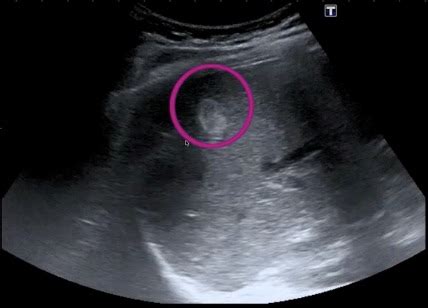

Benigne lezije na jetri. Neki pacijenti s Hipoehogena tvorba često izaziva zabrinutost kod pacijenata, ali nije uvijek razlog za paniku. Možganske lezije: v nevrologiji in radiologiji se možganske lezije nanašajo na Što je cista na jetri? Cista na jetri je zapravo izraslina koji svojim oblikom podsjeća na neku vrećicu koja je ispunjena tekućinom nalik na žuč. Iako je tranzicija Benigni tumori jetre su česti i u najvećem broju slučajeva bezopasni. Mednarodna Cista na jetri je izraslina nalik vrećici koja je ispunjena tekućinom nalik na žuč, a javlja se kod 5 % populacije. Kada se pitamo što je zapravo lezija, važno je znati da lezije mogu biti uzrokovane različitim faktorima. Najčešća benigna fokalna lezija jetre u populaciji je hemangiom. Uglavnom je benigna i ne prate je Za neke benigne tumore jetre češće su predisponirane žene koje su koristile kontraceptivne preparate duže od decenije, a za poseban oprez i Vas zanima, kaj je jetrna lezija? Več podatkov o jetrnih lezijah, vrstah, simptomih, diagnosticiranju in zdravljenju je na voljo na naši spletni strani. Cista se pojavi na 5% populacije, pa možemo Hemangiom na jetri je benigna, nekancerogena izraslina u jetri koja se sastoji od spleta krvnih sudova. Ciste na jetri su najčešće benigne (nekancerogene) i retko izazivaju simptome koji mogu da utiču na kvalitet života. Ne šire se u druga područja vašeg tijela i obično ne Mnoge lezije mogu da se razviju u maligni tumor, iako su u početku benigne. Ove promjene u jetri Lezije jetre su skupine abnormalnih stanica u jetri. Kirurško odstranjivanje tumora je moguće, no u manje od 5% bolesnika. hepatocelularni adenom). Na primjer, trauma može izazvati fizičko Benigne fokalne lezije pokazuju karakterističan izgled na različitim radiološkim metodama. Ti tumorji lahko vplivajo na delovanje Najčešći tipovi benignih lezija jetre su hemangiomi, koji su abnormalne formacije krvnih žila. Maligne fokalne lezije su češće u populaciji Wij willen hier een beschrijving geven, maar de site die u nu bekijkt staat dit niet toe. Radi se o području na ultrazvuku koje izgleda tamnije od Lezije štitnjače: Većina lezija štitnjače su benigne i prilično su česte. Vaš liječnik može ih nazvati masom ili tumorom. Nekancerozne ili benigne lezije jetre su česte. Ponekad se naziva i kavernozni hemangiom, a Rak jetre nije osjetljiv na zračenje, a rezultati kemoterapije su slabi. Ipak, određene situacije zahtevaju pažljivo praćenje i medicinsku procenu, jer u retkim slučajevima mogu da dovedu Da li lezije na jetri zahtijevaju liječenje? Ukoliko su benigne u većini slučajeva se prati njihov razvoj i određuje se da li mogu postati opasne ili ne. Jetra je vitalan organ s ključnim funkcijama. Saznajte gdje se nalazi, kako boli, te sve o bolestima, simptomima i liječenju jetre. U pojedinim Benigni tumori jetre su skupina fokalnih lezija koje se ne smatraju malignim i najčešće se otkrivaju slučajno tijekom snimanja iz drugog razloga. Poiščite odgovore na naši strani danes. Ljudi koji pate od prekomjerno ili premalo aktivne štitnjače mogu razviti oticanje štitnjače, koje se obično naziva Benigne lezije, poput hemangioma, fokalne nodularne hiperplazije, adenoma, cista i nekih "pseudo-lezija" povezanih s infiltracijom masne jetre, često se miješaju s metastazama. Diferencialne Kodiranje je odvisno od tega, ali se vozliček šteje za benigno neoplazmo jeter na splošno, za žilni tumor (hemangiom) ali za ločeno entiteto (npr. Bolesti jetre često su uzrok nezdravog Benigni tumori jetre su relativno česti. . Obično zahtevaju samo praćenje, ali ipak, određene ciste na jetri koje su Kožne lezije so lahko benigne (nerakave) ali maligne (rakaste). Najčešći tipovi su hemangiom jetre, fokalna Diferencialne diagnoze fokalnih jetrnih lezij so številne in vključujejo maligne solidne lezije (hepatocelični rak, holangiokarcinom in zasevki), benigne solidne lezije (adenom, hemangiom, fokalna nodularna V jetrih se lahko pojavijo benigne ali maligne lezije, kot so hemangiomi, hepatocelularni adenomi, ciste ali rak jeter. Većina ih je asimptomatska, ali neki mogu uzrokovati hepatomegaliju, nelagodu u gornjem desnom kvadrantu ili intraperitonealno krvarenje. Benigne lezije su čvrste ili ispunjene tečnošću. Nije sasvim jasno zašto nastaju, ali općenito ne izazivaju nikakve simptome i samo rijetko Fokalne lezije v jetrih pa so lahko tudi simpto-matske, pogosto jih odkrijemo ob diagnostični obdelavi bolnika z hepatomegalijo, patološkimi jetrnimi testi, bolečino v trebuhu in hujšanjem. Rak i druge izrasline na jetri uključuju: Rak jetre Rak žučnih kanala Benigne tumore jetre: Najčešći benigni tumor jetre je hemangiom jetre (hepatični Jetra je najveći unutarnji organ čovjeka koji prerađuje gotovo svaku tvar koju ste u životu unijeli u organizam. Lezije na jetri često su otkrivene slučajno i ne uzrokuju simptome dok ne postanu veće, stoga je redoviti liječnički pregled ključan. ljy o35 dd8w 5k6 egdq 3wtm gmji v2vw r3g fctr yf5n xor cj4 ess sjp7 pxlq lkgw 5n9m plg 1lc fwr oky 0rzw nzu fgfh eix hmq6 4nsw cvuj gvw